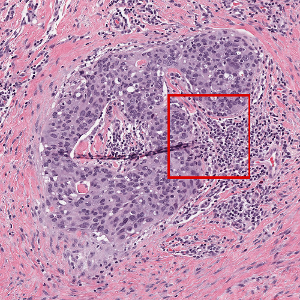

In the histopathology literature, CNN architectures tend to follow a linear trend with a series of layers sequentially arranged from an input layer to a softmax output layer [9, 8]. Recently, however, there have been adaptations to this structure to encourage multiscale information at various stages in the CNN design. For example Xu et al. [17] proposed a multichannel side supervision CNN which merges edges and contours of glands at each convolution layer for gland segmentation. In cell nuclei classficiation, Buyssens et al. [2] learn multiple CNNs in parallel with input images at various resolutions before aggregating classification scores. These methods have shown to be particularly advantageous in histology images as it mimics pathologists’ interpretation of digital slides when viewed at multiple objectives (Fig. 1).

We evaluated the performance of the proposed transition module using a dataset of image patches extracted and labelled from breast WSIs scanned at x magnification by a Scanscope XT (Aperio technologies, Leica Biosystems) scanner. Each RGB patch of size x was hand selected from WSIs, each one from a single patient, by a trained pathologist. Biopsies were extracted from patients with invasive breast cancer and subsequently received neo-adjuvant therapy; post neoadjuvant tissue sections revealed invasive and/or ductal carcinoma in situ. -fold cross validation was used to evaluate the performance of this dataset. Each image patch was confirmed to contain either tumor or healthy tissue by an expert pathologist. “Healthy” refers to patches which are absent of cancer cells but may contain healthy epithelial cells amongst other tissue structures such as stroma, fat etc. Results are reported over epochs.